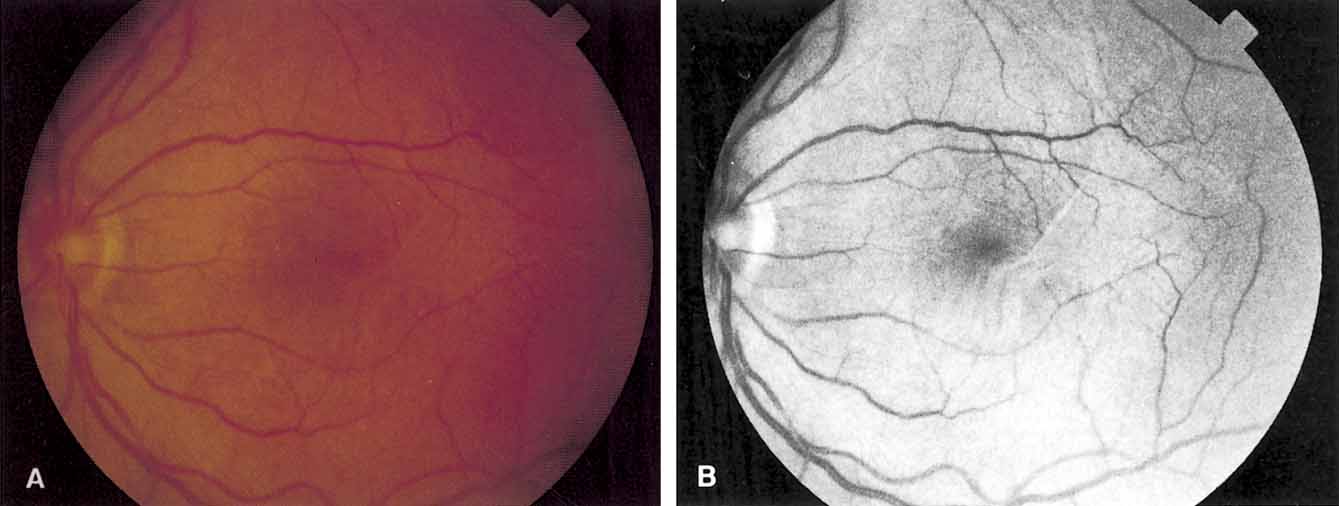

Fundus photography and fluorescein angiography are useful tools in the diagnosis of a macular hole. Stereo color photography helps document the stage, size, and configuration of the hole so that any changes may be detected easily. However, it is important to obtain similar stereo images for serial comparison. Monochromatic photography with use of 490- to 610-nm filters is another useful tool. Monochromatic photos help identify subtle vitreoretinal interface changes.11 Fluorescein angiography, although useful in differentiating a true macular hole from a simulating lesion, can be misleading. The increased transmission of choroidal fluorescence that is associated with macular holes can reverse spontaneously.12 It may also reverse after successful surgical treatment.13